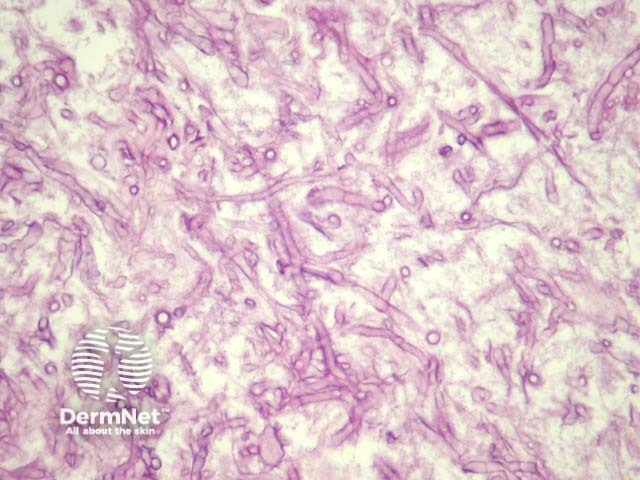

The fungal forms of mucormycosis are broad, non-septate hyphae (figure 1). They are wider than Aspergillus species and branch irregularly. The angle of branching is greater than other organisms, and usually approaches 90° (figure 2, arrow)

Mucormycosis organisms may easily be seen on haematoxylin and eosin sections (figure 1). Special stains with PAS (figure 2) or GMS can be used to highlight the organisms and allow a clearer assessment of the morphology.